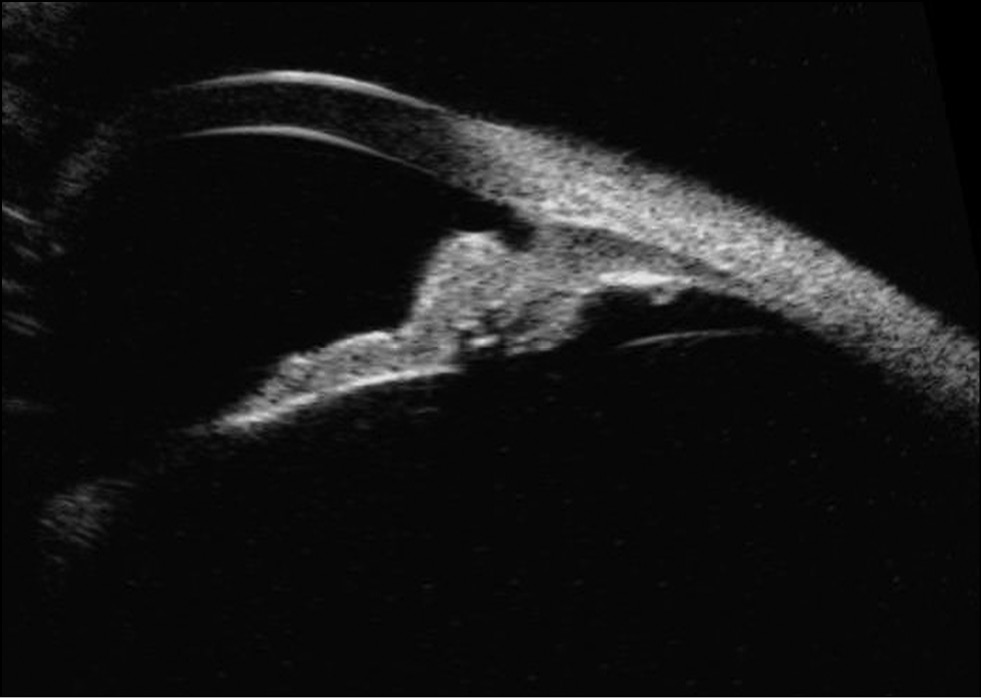

Пациент С., 2 года. У ребёнка в возрасте 6 месяцев родители заметили новообразование на радужке левого глаза, которое постепенно увеличивалось в размерах. При биомикроскопии отмечено пигментированное кистовидное образование с сосудами на поверхности на радужке с 12 до 2 часов, смещающее радужку кзади и контактирующее с роговицей, УПК в этом отделе не визуализируется. В августе 2021 г. ребёнок осмотрен под общим наркозом с максимальным мидриазом в отделе офтальмоонкологии и радиологии Центра. На основании клинической картины, данным ультразвукового исследования и ультразвуковой биомикроскопии сделано заключение, что у ребёнка имеется иридоцилиарная киста, закрывающая УПК с 12 до 2 часов без признаков гипертензии и воспаления. Было рекомендовано динамическое наблюдение.

При повторном осмотре в январе 2022 г. у ребёнка 2 лет отмечен прогрессирующий рост врождённой кисты радужки (за 5 месяцев). Киста занимала весь верхне-наружный отдел радужки с 12 до 4 часов, увеличилась в объёме, заполнила всю переднюю камеру в верхне-наружном секторе с плоскостным сращением передней стенки кисты с роговицей в этом секторе, деформировала зрачок, не доходя до зрачкового края 1 мм (рис. 6).

Рис. 6. Врождённая киста радужки.

Пациенту проведена ИАГ-лазерная цистотомия и цис-тодеструкция врождённой кисты радужки, передней камеры, рассечение сращений кисты с роговицей, диод-лазерная коагуляция центрального края кисты. Далее больному рекомендовано динамическое наблюдение.